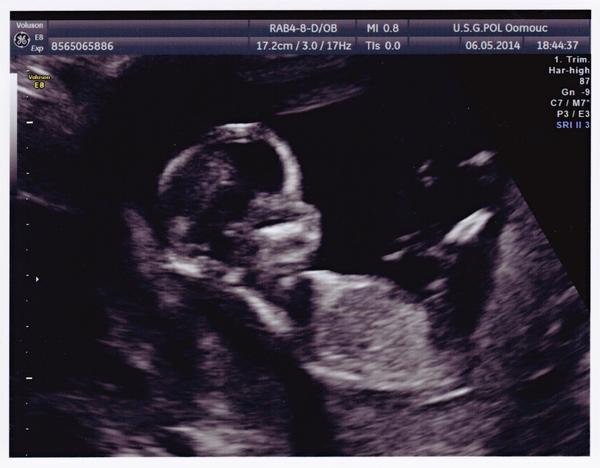

Holky tak konečně i já píši. Tak teda ráno v 11.15 poradna u me gyndařky, myslela jsem, že UTZ nebude, ale ma strach, jak ja a dělala. Miminko se krasne mrskalo, pohlavi zachytit neslo, bylo to pry 13+4 a 7,5 cm. Vecer screening, miminko v poradku, vizualizace ale spatne, pry je nekde hodne hluboko, takze organy nebylo mozne ještě prozkoumat, ale odpovida 13+3 a 7,32 cm, termin porodu 8.11. Geneticky naprosto v poradku, cisla ještě lepsi nez u toho nepovedeného tehu. Pohlavi videt neslo vůbec.

@kifsepixam krásné miminko!! Držím palce, ať je vše v pořádku, tentokrát už musí 🙂

Holky, jak já tady vidím ty vaše fotky z ultrazvuku, já se tak těším, až budu zase těhotná!!! No už aby to bylo...

@kifsepixam Kočko, to jsou krásné zprávy a obrázek nádherný! Doufám, že tě mimísek zase o kousek víc přesvědčil, že to prostě nevzdá a že je to veliký bojovník.. jako maminka! Tak ho drobečka pozdravuj a pupíkovi posílám pohlazení 🙂